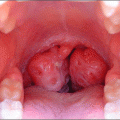

Diş eti şişme nedenleri arasında birçok farklı faktör bulunabilir. Belirtilerine geçmeden önce genel yapısına kısaca değinelim. Diş eti şişmesinin meydana geldiği yer dişlerinizin arası, kenarı ya da üstü şeklinde görülebilir. Bazı durumlarda diş altı kısımlarında da çıkabilmektedir. Ön diş ya da arka diş gözetmeksizin her an karşımıza çıktığı görülür. O bölgede bir kızarıklık meydana gelir. Bazen yanak kısımlarından bu şişlik kendisini belli edebilir.

diş eti şişmesi

Diş eti neden şişer diyenleriniz muhakkak vardır. Bunların başında diş eti iltihabı, diş çürüklerinin oluşturduğu iltihap ve en çok karşılaşılan durum ise yiyecekleri tüketirken dikkat etmememizden kaynaklıdır. Örneğin; elma yerken ön dişlerimize büyük görev düşer. Mesela elmayı ısırıp lokla halinde çiğneme öncesinde ısırıp koparmak gerekir. Dişlerinizi elmanın içine çok batırarak bunu yaptığınızda alt ve üst ön diş etlerinizde kızarıklık ve şişmeyi çok rahat görebilirsiniz. Hatta bu durum sadece elma ile sınırlı örneklendirilmez.